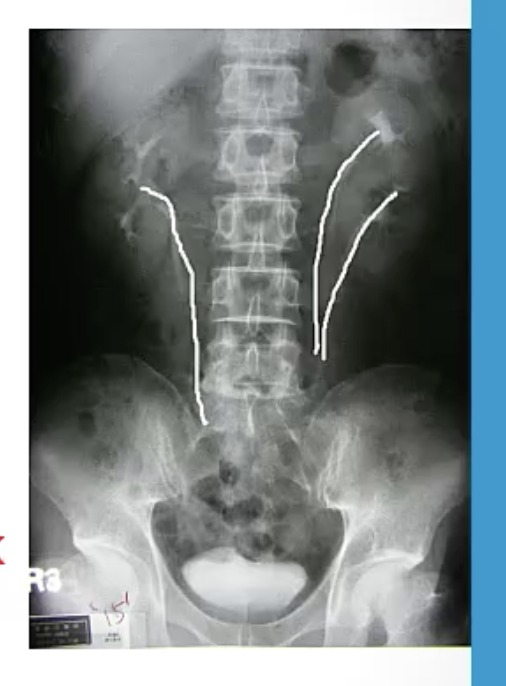

Duplex Collecting System

A

two uteric buds or a bifurcation of a ureteric bud; may lead to poor urine flow, hydronephrosis and UTIs; associated w *vesicoureteral reflux